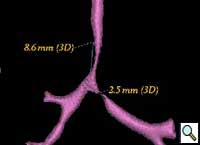

Patient was further evaluated with 64-slice MD CT angiogram which revealed double aortic arch, with balanced arches encircling the trachea and esophagus (Figure 1). The distal trachea and proximal left bronchus were compressed by the vascular ring (Figure 2, 3).